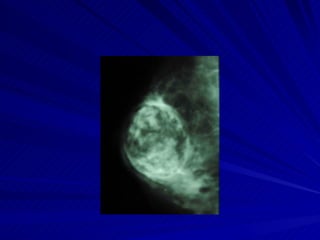

fibroadenoma En las jóvenes se presenta en la rx.como un nódulo denso de bordes bien definidos.  Ecográficamente, es hipoecoico, de bordes definidos, sin o con leve refuerzo posterior. Pueden ser únicos o múltiples, solo cuando se calcifican el diagnóstico es de certeza.(birads 2).

Fibroadenoma: cuando se calcifica el diagnostico  es seguro Calcificación en forma de  pochoclo o popcorn.

fibroadenoma En lasjóvenes se presenta en la rx.como un nódulo denso de bordes bien definidos. Ecográficamente, es hipoecoico, de bordes definidos, sin o con leve refuerzo posterior. Pueden ser únicos o múltiples, solo cuando se calcifican el diagnóstico es de certeza.(birads 2).

Fibroadenoma: cuando secalcifica el diagnostico es seguro Calcificación en forma de pochoclo o popcorn.